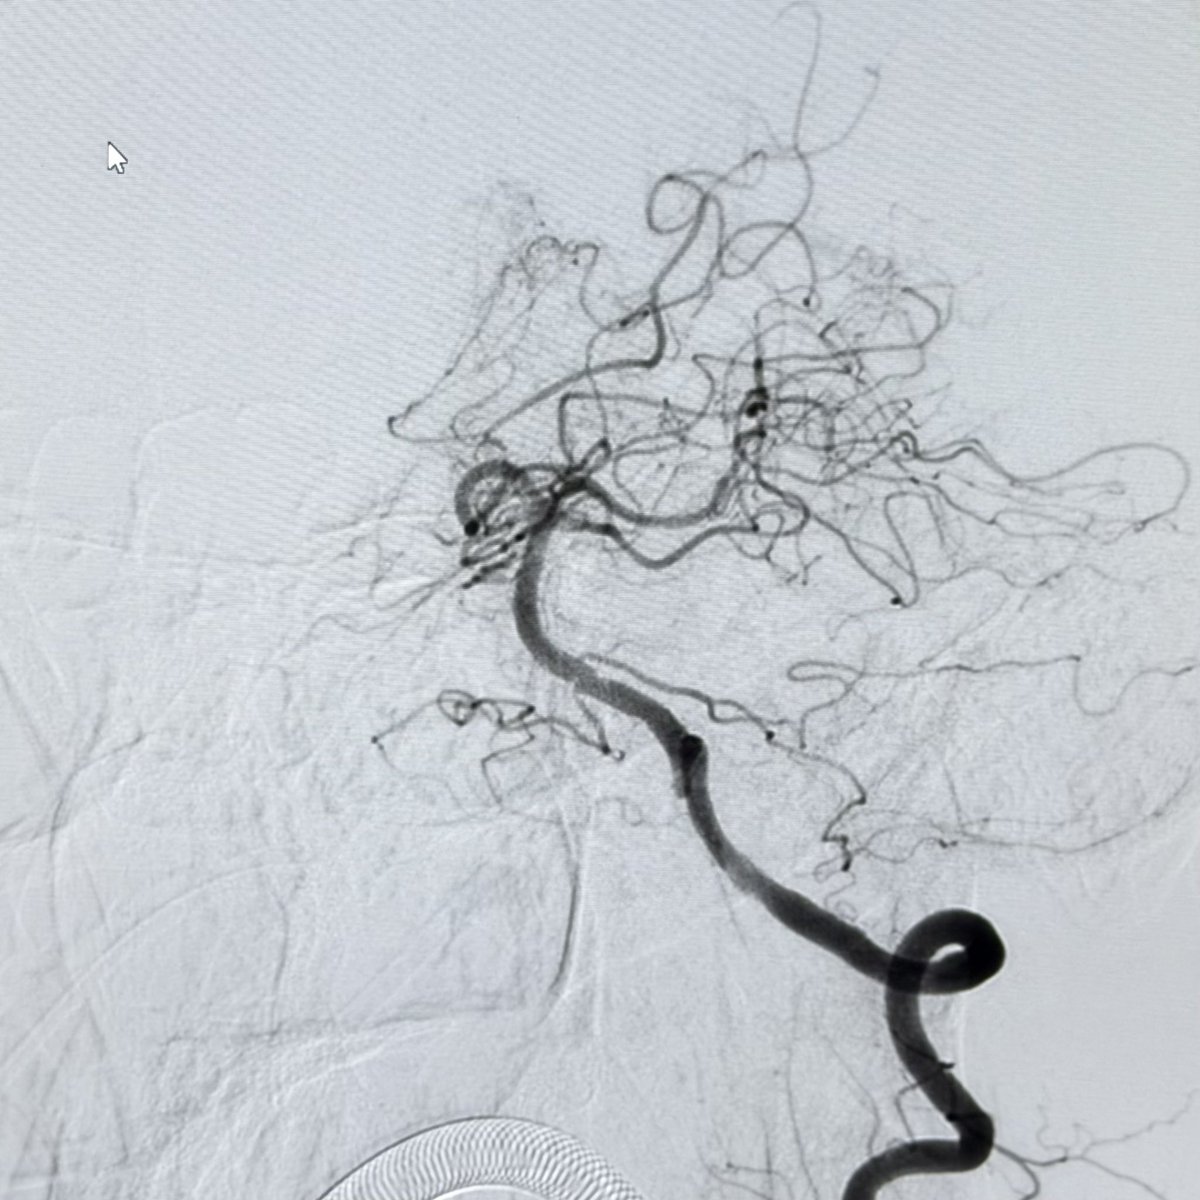

This 🧔♂️ presents with a subarachnoid haemorrhage in the left suprasellar cistern

DSA shows an infundibulum/ aneurysm of the left PCom. To coil or not was a conundrum. Every expert has a different take

The size is 3.4 mm x 2.6 and it is located in the region of the bleed.

@bobvarkey @PascalJabbourMD given the SAH presentation, matching location, and size exceeding 3 mm, I'd treat this as a ruptured aneurysm and proceed with endovascular coiling ASAP